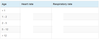

Gross motor milestones

3 months

Little or no head lag on being pulled to sit

Lying on abdomen, good head control

Held sitting, lumbar curve

Gross motor milestones

6 months

Lying on abdomen arms extended

Lying on back, lifts and grasps feet

Pulls self to sitting

Held sitting, back straight

Rolls front to back

Gross motor milestones

7-8m

Sits without support

(Refer at 12m)

Gross motor milestones

9 months

Pulls to standing

Crawls

Gross motor milestones

12m

Cruises

Walks with one hand held

Gross motor milestones

13-15m

Walks unsupported

(Refer at 18m)

Gross motor milestones

2y

Runs

Walks upstairs and downstairs holding onto rail

Gross motor milestones

3y

Rides a tricycle using pedals

Walks up stairs without holding a rail

Gross motor milestones

4y

Hops on one leg